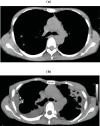

(a) Chest CT in a 48-year-old woman with PPFE. (b) Chest CT taken after 4 years. Both CT scans were sliced at the level of the 6th thoracic vertebra. The ratio of the anterior–posterior diameter of the thorax to the transverse diameter of the thorax became lower after 4 years of disease progression.